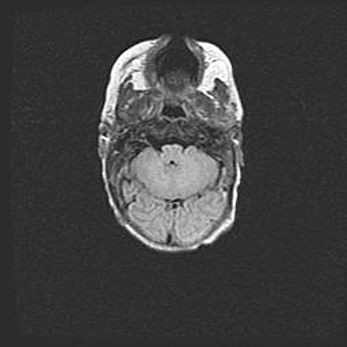

Множественные кисты обоих полушарий головного мозга, наибольшая из них в правой затылочной области. Ассиметричная атрофическая гидроцефалия.

Возраст: 7 месяцев

Вес: 5660 г

Пол: мужской

Окружность головы: 41,5 см

Срок гестации: 28-29 недель

Кисты головного мозга развиваются в результате многоочаговых некрозов вещества мозга и возникают вследствие перенесенной перинатальной инфекции, менингитов, энцефалитов, асфиксии, родовой травмы, расстройств мозгового кровообращения различного генеза. Образованию кист в веществе головного мозга плодов и новорожденных способствуют такие факторы, как высокое содержание в нем воды, недостаточная (или отсутствие) миелинизация и слабая астроглиальная реакция на повреждение.

Кисты могут сочетаться с гидроцефалией и другими поражениями головного мозга.